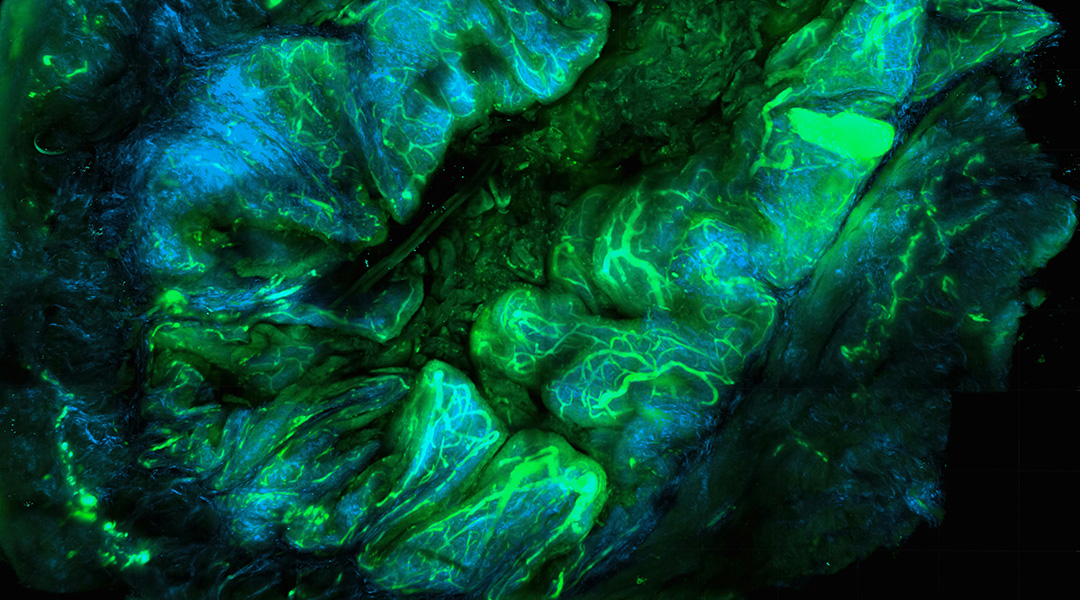

Peptides light up in the brain for early diagnosis of Alzheimer’s

Peptide-laden vesicles light up in the presence of amyloid beta, providing an early diagnostic test (and possible treatment) for Alzheimer’s.

Peptides light up in the brain for early diagnosis of Alzheimer’s

Peptide-laden vesicles light up in the presence of amyloid beta, providing an early diagnostic test (and possible treatment) for Alzheimer’s.